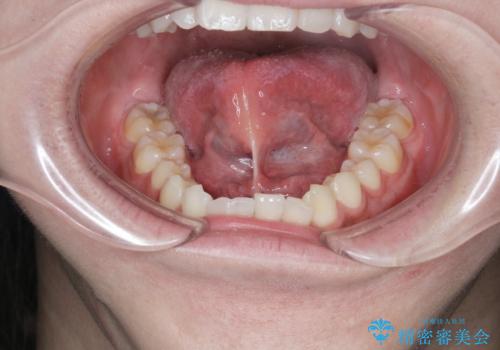

滑舌の改善 舌小帯の形成術

- 友人に滑舌の悪さを指摘され、改善を求めて来院されました。

舌下部に位置する小帯(ヒダ)の長い付着が認められるので、形成術を行うことで滑舌の改善を計画します。